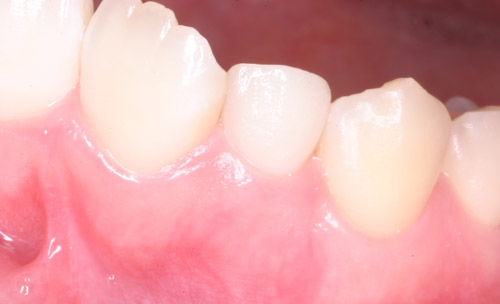

治療前

治療後

ファイバーコア